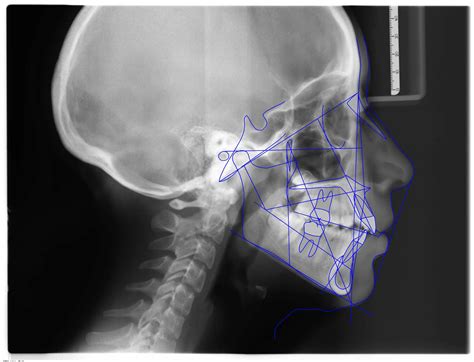

Diagnóstico: El análisis de las fotografías faciales reveló una paciente dolicofacial, cara con forma ovalada, perfil recto, nariz recta, labios competentes, sonrisa positiva, la línea media facial coincide con la línea media dental. En el examen clínico intraoral se observó: mordida abierta anterior, mordida cruzada posterior, las líneas medias superior e inferior dentales no coinciden, clase I molar izquierda y derecha, clase I canina izquierda y derecha; forma de la arcada paraboloide, ligero apiñamiento en la zona anterior superior e inferior.

Resultados: Los resultados fueron obtenidos con el análisis y comparación de las fotografías modelos y cefalometrías de inicio y finalización del tratamiento. La fotografía facial de sonrisa mostró una mejora estética importante, se corrigió la desviación de la línea media y el apiñamiento dental, no se observó una diferencia en cuanto a la exposición dental comparada con la fotografía inicial, el perfil se mantuvo como al inicio de tratamiento.

Al realizarse la comparación de las fotografías iniciales y finales se la alineación y nivelación de las arcadas superior e inferior, el cierre de la mordida abierta anterior que dio como resultado una sobremordida vertical de 3mm y una sobremordida horizontal 4mm, también la consolidación de la clase I molar y canina, mordida cruzada de los segundos molares superiores.